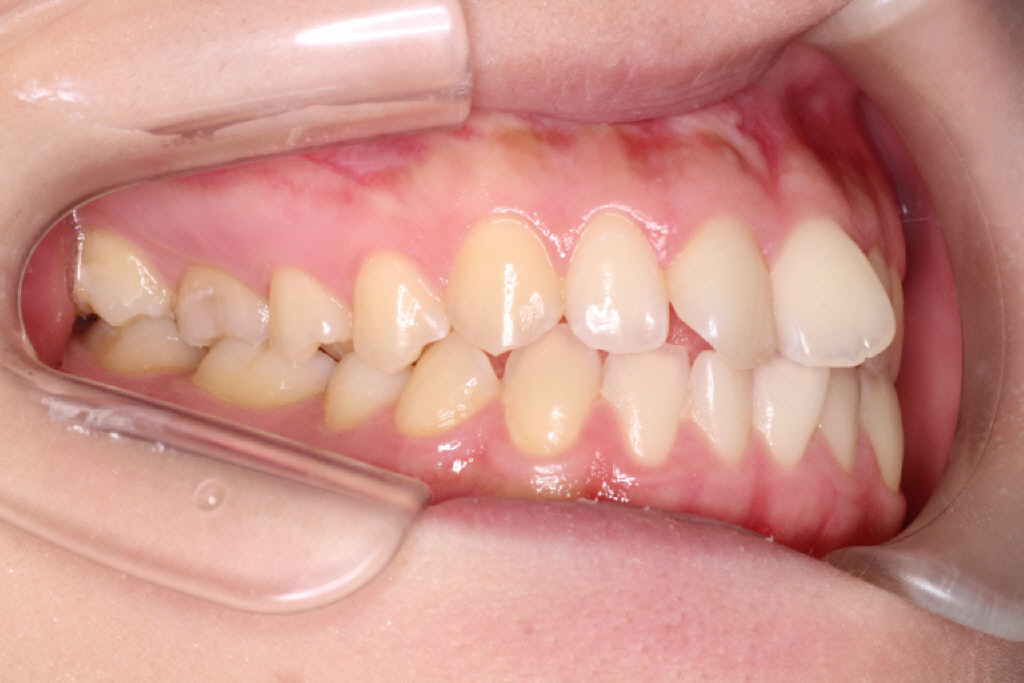

2回目のインビザラインのクリーンチェックです。最後のアライナーの12番です。

上のクリーンチェックでは前歯に隙間は空かない予定でしたが、

私は、舌癖(舌を前に出してしまう)があることがわかりました。

舌を前に出してしまうと、前歯を押してしまうためインビザラインで動かしていくときに妨げになってしまいます。